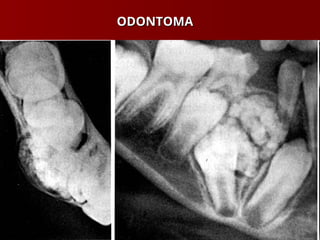

 Odontoma

ODONTOMA

TUMORES ODONTOGÊNICOS TUMORES ODONTOGÊNICOS Ameloblastoma Ameloblastoma  Cementoma – Displasia Cementossea Cementoma – Displasia Cementossea Focal Focal  Odontoma Odontoma